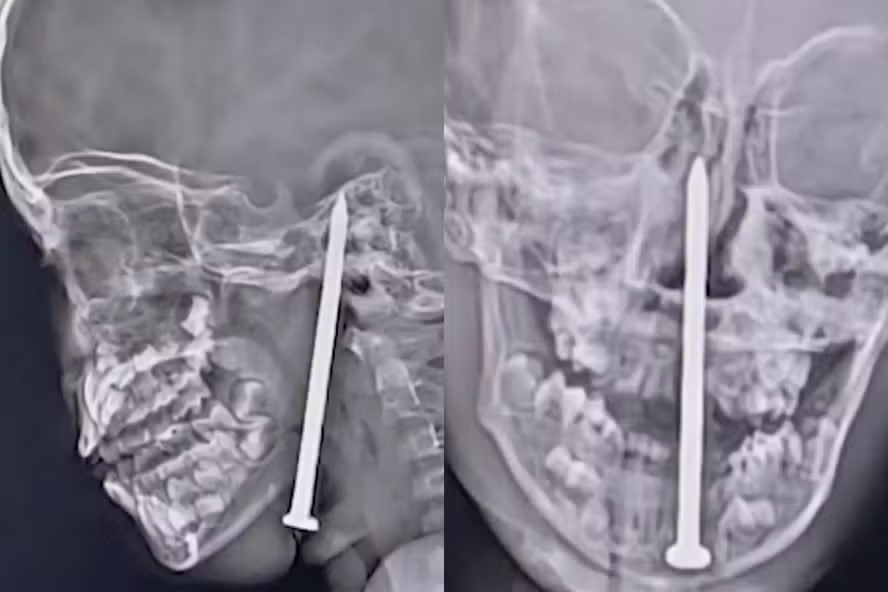

Imagens de ressonância magnética divulgadas pelo hospital mostraram que o prego estava inserido desde a parte inferior da mandíbula até o interior do crânio, evidenciando o quão próximo esteve de causar um dano cerebral fatal. Profissionais do hospital explicaram que o objeto poderia ter causado a morte se tivesse atingido um vaso sanguíneo importante ou uma área distinta do cérebro.

“Durante os exames, descobrimos que o prego havia migrado do pescoço para o cérebro sem atingir nenhum vaso vital. Após consultas com especialistas, decidimos seguir com a cirurgia, que era bastante complexa”, relatou o médico Sandip Tiwari à "ETV Bharat".

Já Samir Misra, da equipe de cirurgia de trauma, detalhou ao "The Hindustan Times" que o procedimento levou cerca de quatro horas e exigiu extrema precisão, pois qualquer erro poderia ter consequências fatais.